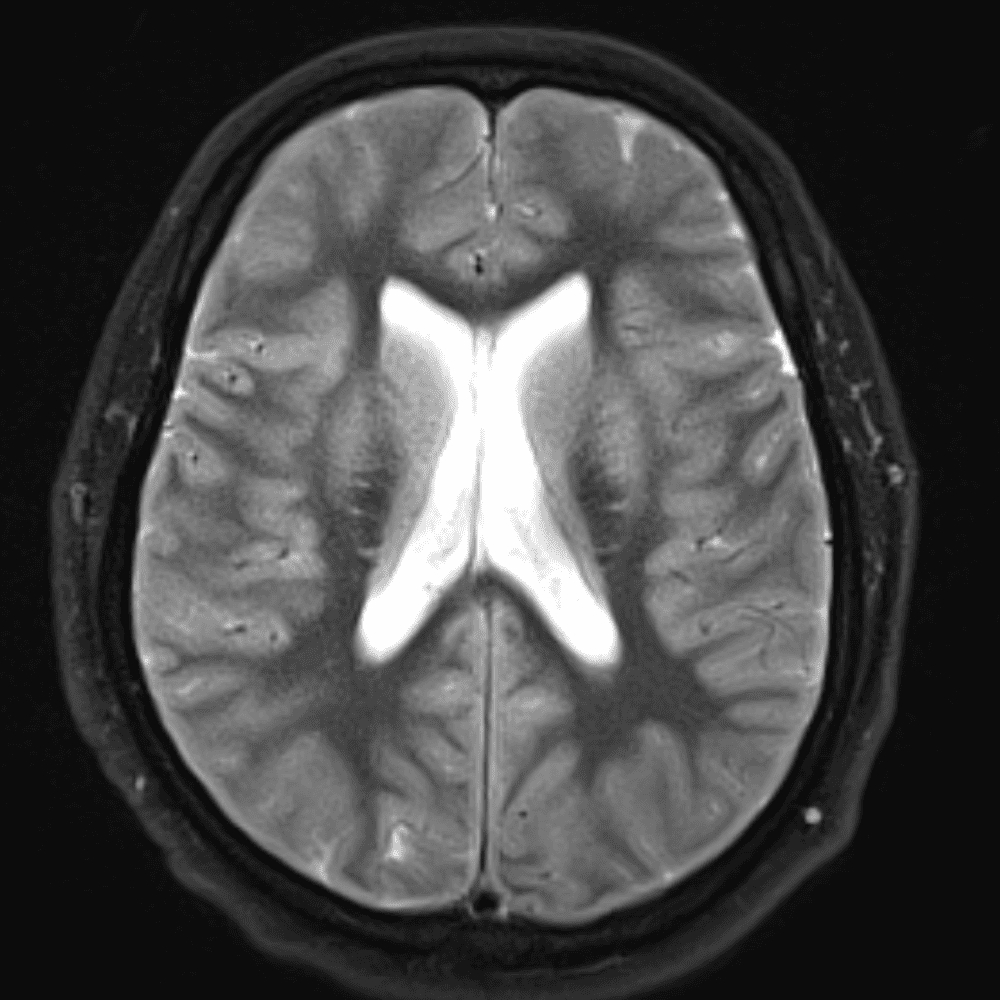

๋‹น์ง ์‹œ ํ”ํžˆ ๋ณผ ์ˆ˜ ์žˆ๋Š” ์‚ฌ๋ก€์˜ ์ „ํ˜•์ ์ธ ์˜ˆ๋ฅผ ํฌํ•จํ•ฉ๋‹ˆ๋‹ค.

39 ์‚ฌ๋ก€

์—ฐ์Šต

๋ฏธ๋ฌ˜ํ•˜๊ฑฐ๋‚˜ ์–ด๋ ค์šด ์‚ฌ๋ก€์™€ ์ผ๋ถ€ ์ •์ƒ ์‚ฌ๋ก€๋ฅผ ํฌํ•จํ•˜์—ฌ ๋‹น์ง์„ ์‹œ๋ฎฌ๋ ˆ์ด์…˜ํ•ฉ๋‹ˆ๋‹ค.

50 ์‚ฌ๋ก€